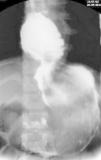

Niña de 8 años de edad, remitida a nuestro centro con historia clínica de dolor abdominal, náusea y disminución del apetito. Los estudios radiológicos mostraron una gran masa en el estómago que se extendía hacia el duodeno (fig. 1); la endoscopia digestiva puso en evidencia la presencia de un tricobezoar de pelos y restos de fibras de ropa que ocupaba la casi totalidad de la cavidad gástrica, extendiéndose hacia el píloro, hasta perderse en el duodeno.